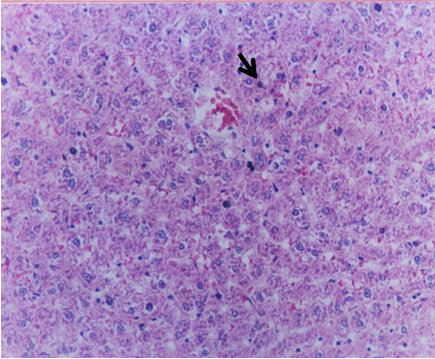

Histopathological results

Our results (Figure 1 [Fig. 1], Figure 2 [Fig. 2], Figure 3 [Fig. 3], Figure 4 [Fig. 4], Figure 5 [Fig. 5], Figure 6 [Fig. 6], Figure 7 [Fig. 7]) revealed that treatment of the PC group with FO or OO supplemented with vitamins E & C led to the best improvement. The histopathological investigation showed apparently normal hepatocytes.

Figure 1: Liver of rat from NC group showing normal histological structure of hepatic lobule (H and E x 200)

Figure 5: Liver of rat from OOEC group showing apparently normal hepatocytes (H and E x 200)